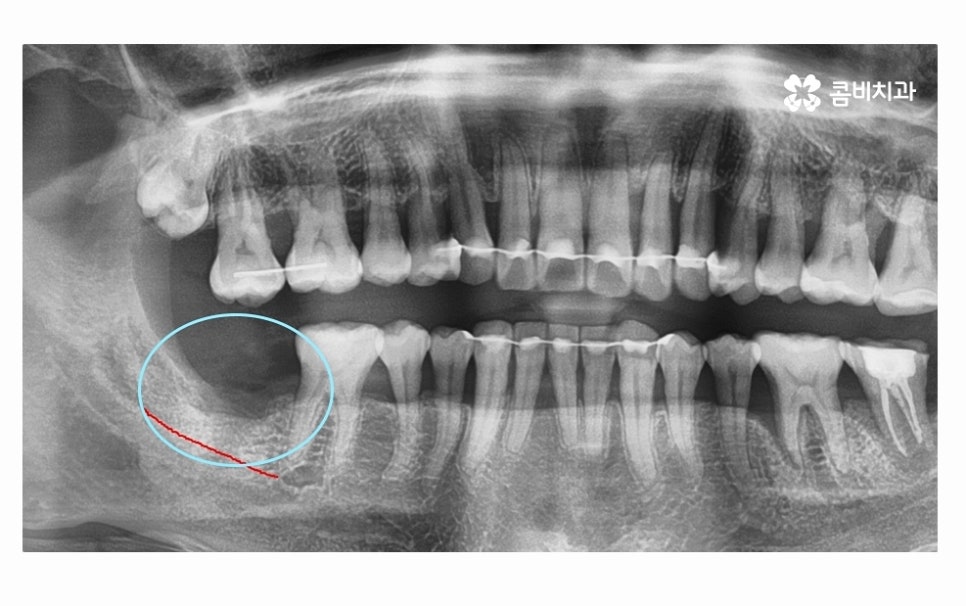

치아를 단단하게 고정해야 하는 잇몸 뼈가 치주염으로 인해

파괴되면 치아를 잃게 될 수 있는데 더 큰 문제는

잇몸에 발생한 염증이 주변 잇몸이나 턱뼈까지 손상을

치아 뿌리 염증이 잇몸질환으로 인해 발생한 경우에는

발치와 잇몸 뼈의 회복, 뼈이식 등의 과정이 필요할 수 있으며

개인별 건강 상태도 충분히 잘 고려해야 하기 때문에

빠른 치료보다는 안전하고 건강하게 시술하는 것이 관건이라고 볼 수 있어요.